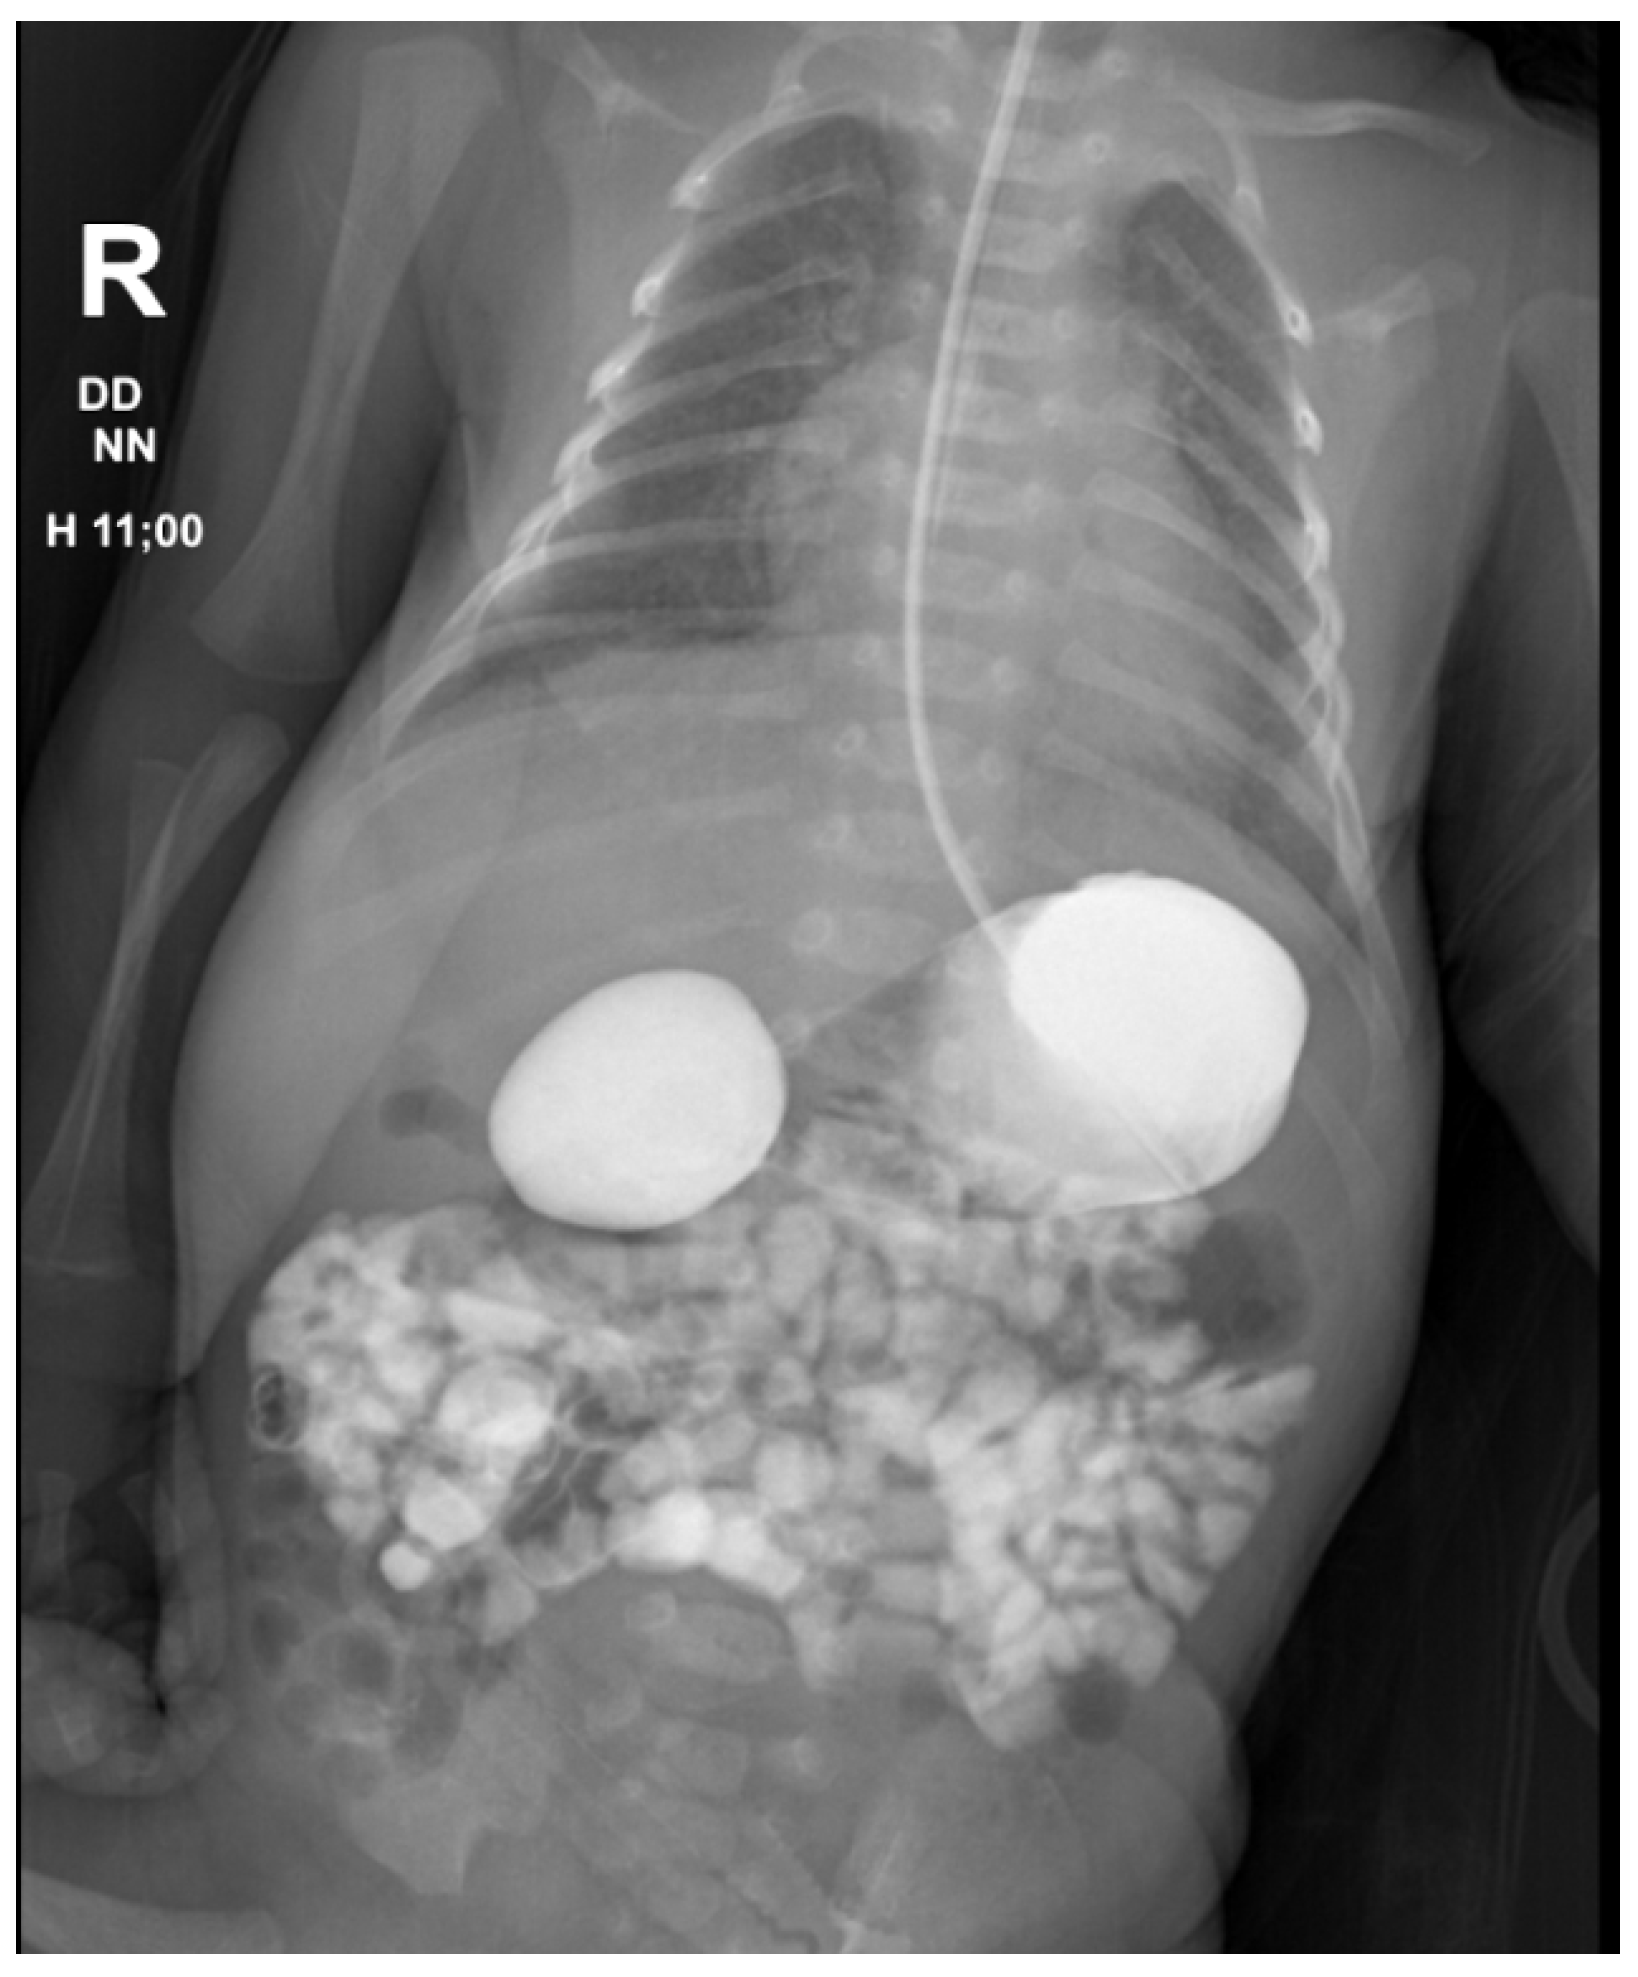

- Koberlein, G.; DiSantis, D. The “double bubble” sign. Abdom. Imaging 2016, 41, 334–335. [Google Scholar] [CrossRef] [PubMed]

- Traubici, J. The Double Bubble Sign. Radiology 2001, 220, 463–464. [Google Scholar] [CrossRef] [PubMed]